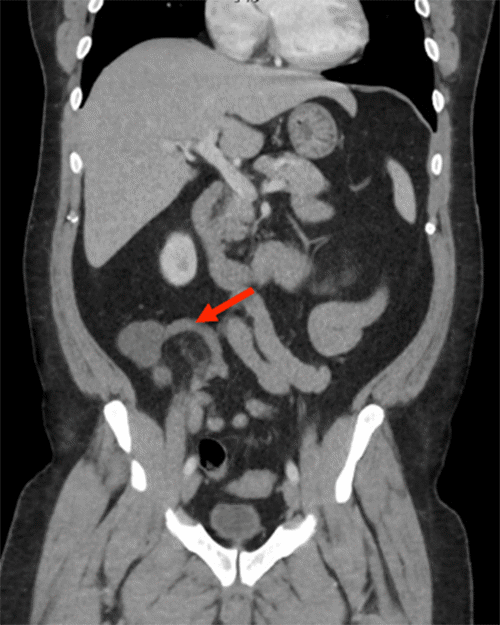

On postoperative day (POD) 12, the patient reported feeling well with no complaints during a routine follow-up clinic visit. Final pathology confirmed acute appendicitis. However, on POD 15, he presented to the emergency department with sudden-onset worsening epigastric abdominal pain and nausea. While a physical exam revealed no concerning findings, laboratory tests showed a mild elevation in white blood cell count (leukocytosis) and lactate levels. A CT scan with contrast identified superior mesenteric vein (SMV) thrombophlebitis (Figure 2). The patient was admitted for non-operative management with serial abdominal examinations and intravenous heparin infusion.

Figure 2. CT Scan Demonstrating Superior Mesenteric Vein (SMV) Thrombophlebitis. Published with Permission